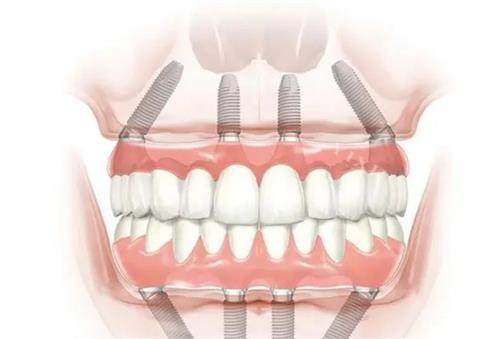

烟台半口/全口种植牙价格参考

半口种植:

半固定种植牙:2万元起(2颗植体+牙桥)

即刻负重种植牙:4万元起

全口种植:

半固定种植牙:4万元起(4颗植体+半年后带牙桥)

即刻负重种植牙:8万元起